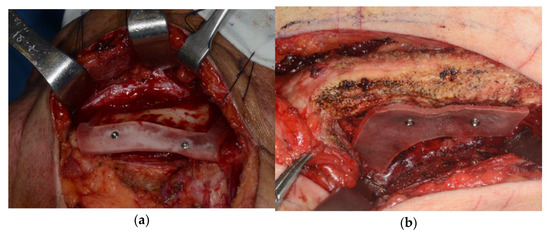

2.1.2. Surgical Technique

2.2.2. Surgical Technique